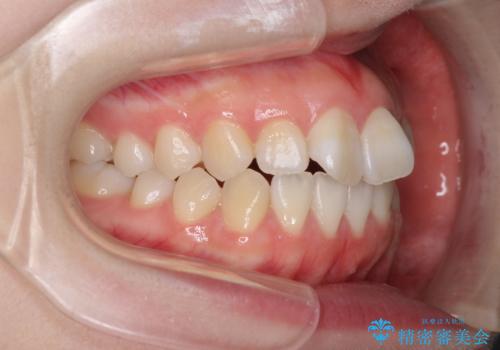

- 前歯の捻れと、ちょっとした出っ張りを気にして来院された患者様です。

歯と歯の間を削る(IPR)ことでデコボコを解消し、インビザラインで整えることとしました。

インビザライン治療特有の奥歯が接触しない時期が続き、当初予定よりも期間がかかりましたが、最終的には安定した咬み合わせと、整った前歯になりました。